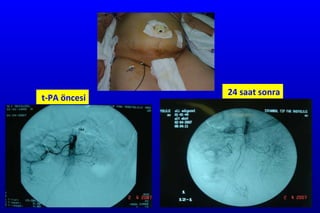

Trombolitik tedavi  (rt-PA )  Mezenter arter kateteriz asyondan  re k ombinant  doku plazm ino j en a k tivat ö r ü  (rt-PA )  5   mg bolus 10 dakika içinde , 1-1.5  mg /st  perfüzyon en fazla 24  saat  T rombolitik tedavi sonrası  (ya rı ömrü 20 d k)  ameliyat yapılabilir  A ritmi  veya  tansiyon değişikl iğine  yol açabilmeleri nedeni ile monitorize hastalarda uygulanmalıdır.

t-PA öncesi 24 saat sonra

Trombolitik tedavi etkinliğiPrim er: Anjiografik başarı Se k ond er: Klinik başarı peritonit ve karın ağrısı Ter siyer: Laparoskopik olarak iskeminin gerilemesi

t-PA öncesi 24saat sonra

• #38 Kontrol angiografi: SMA’ da %70 rekanalizasyon, proksimal jejunal ve ileokolik dalların açıldığı görüldü